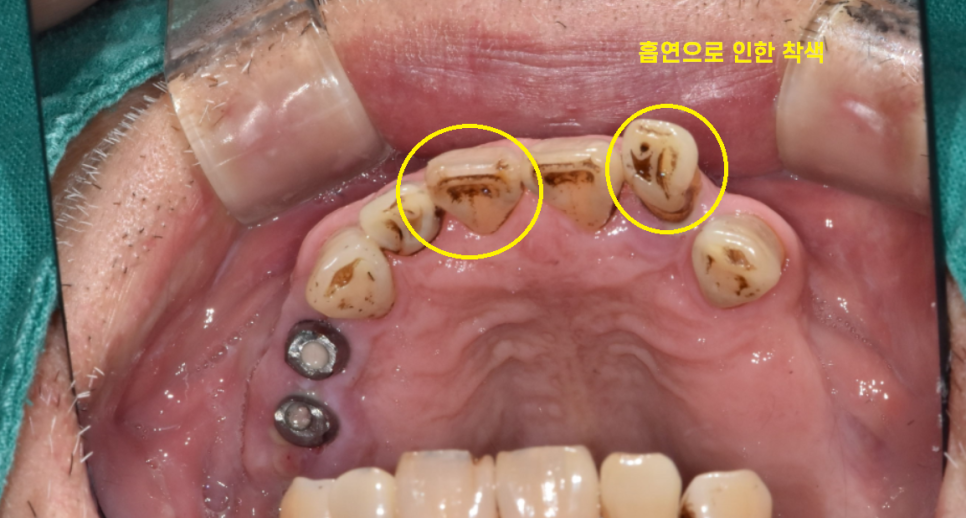

23.12.16

흠...

애연가이시다보니

치아에 착색도 많이 되었습니다.

임플란트 수술과 담배는 천적인데요